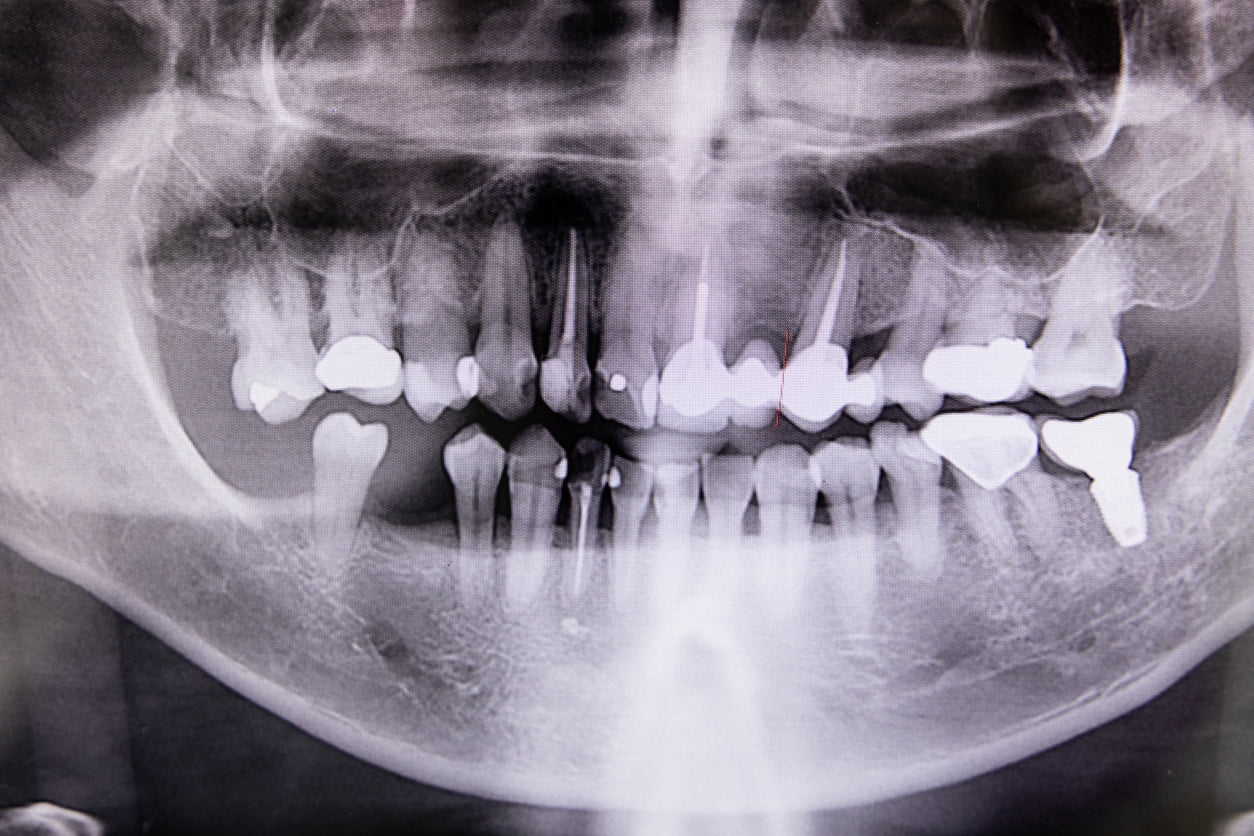

All root canal treatment procedures are performed by isolating the tooth with a rubber dam to provide a clean and saliva-free environment. Root canal treatment may be done in single or multiple visits depending on the complexity of the tooth. In between treatment appointments, medicaments may be placed within the canals and the tooth is covered with a temporary filling. Often, X-rays are taken to determine the length of the root and to monitor the various treatment stages.